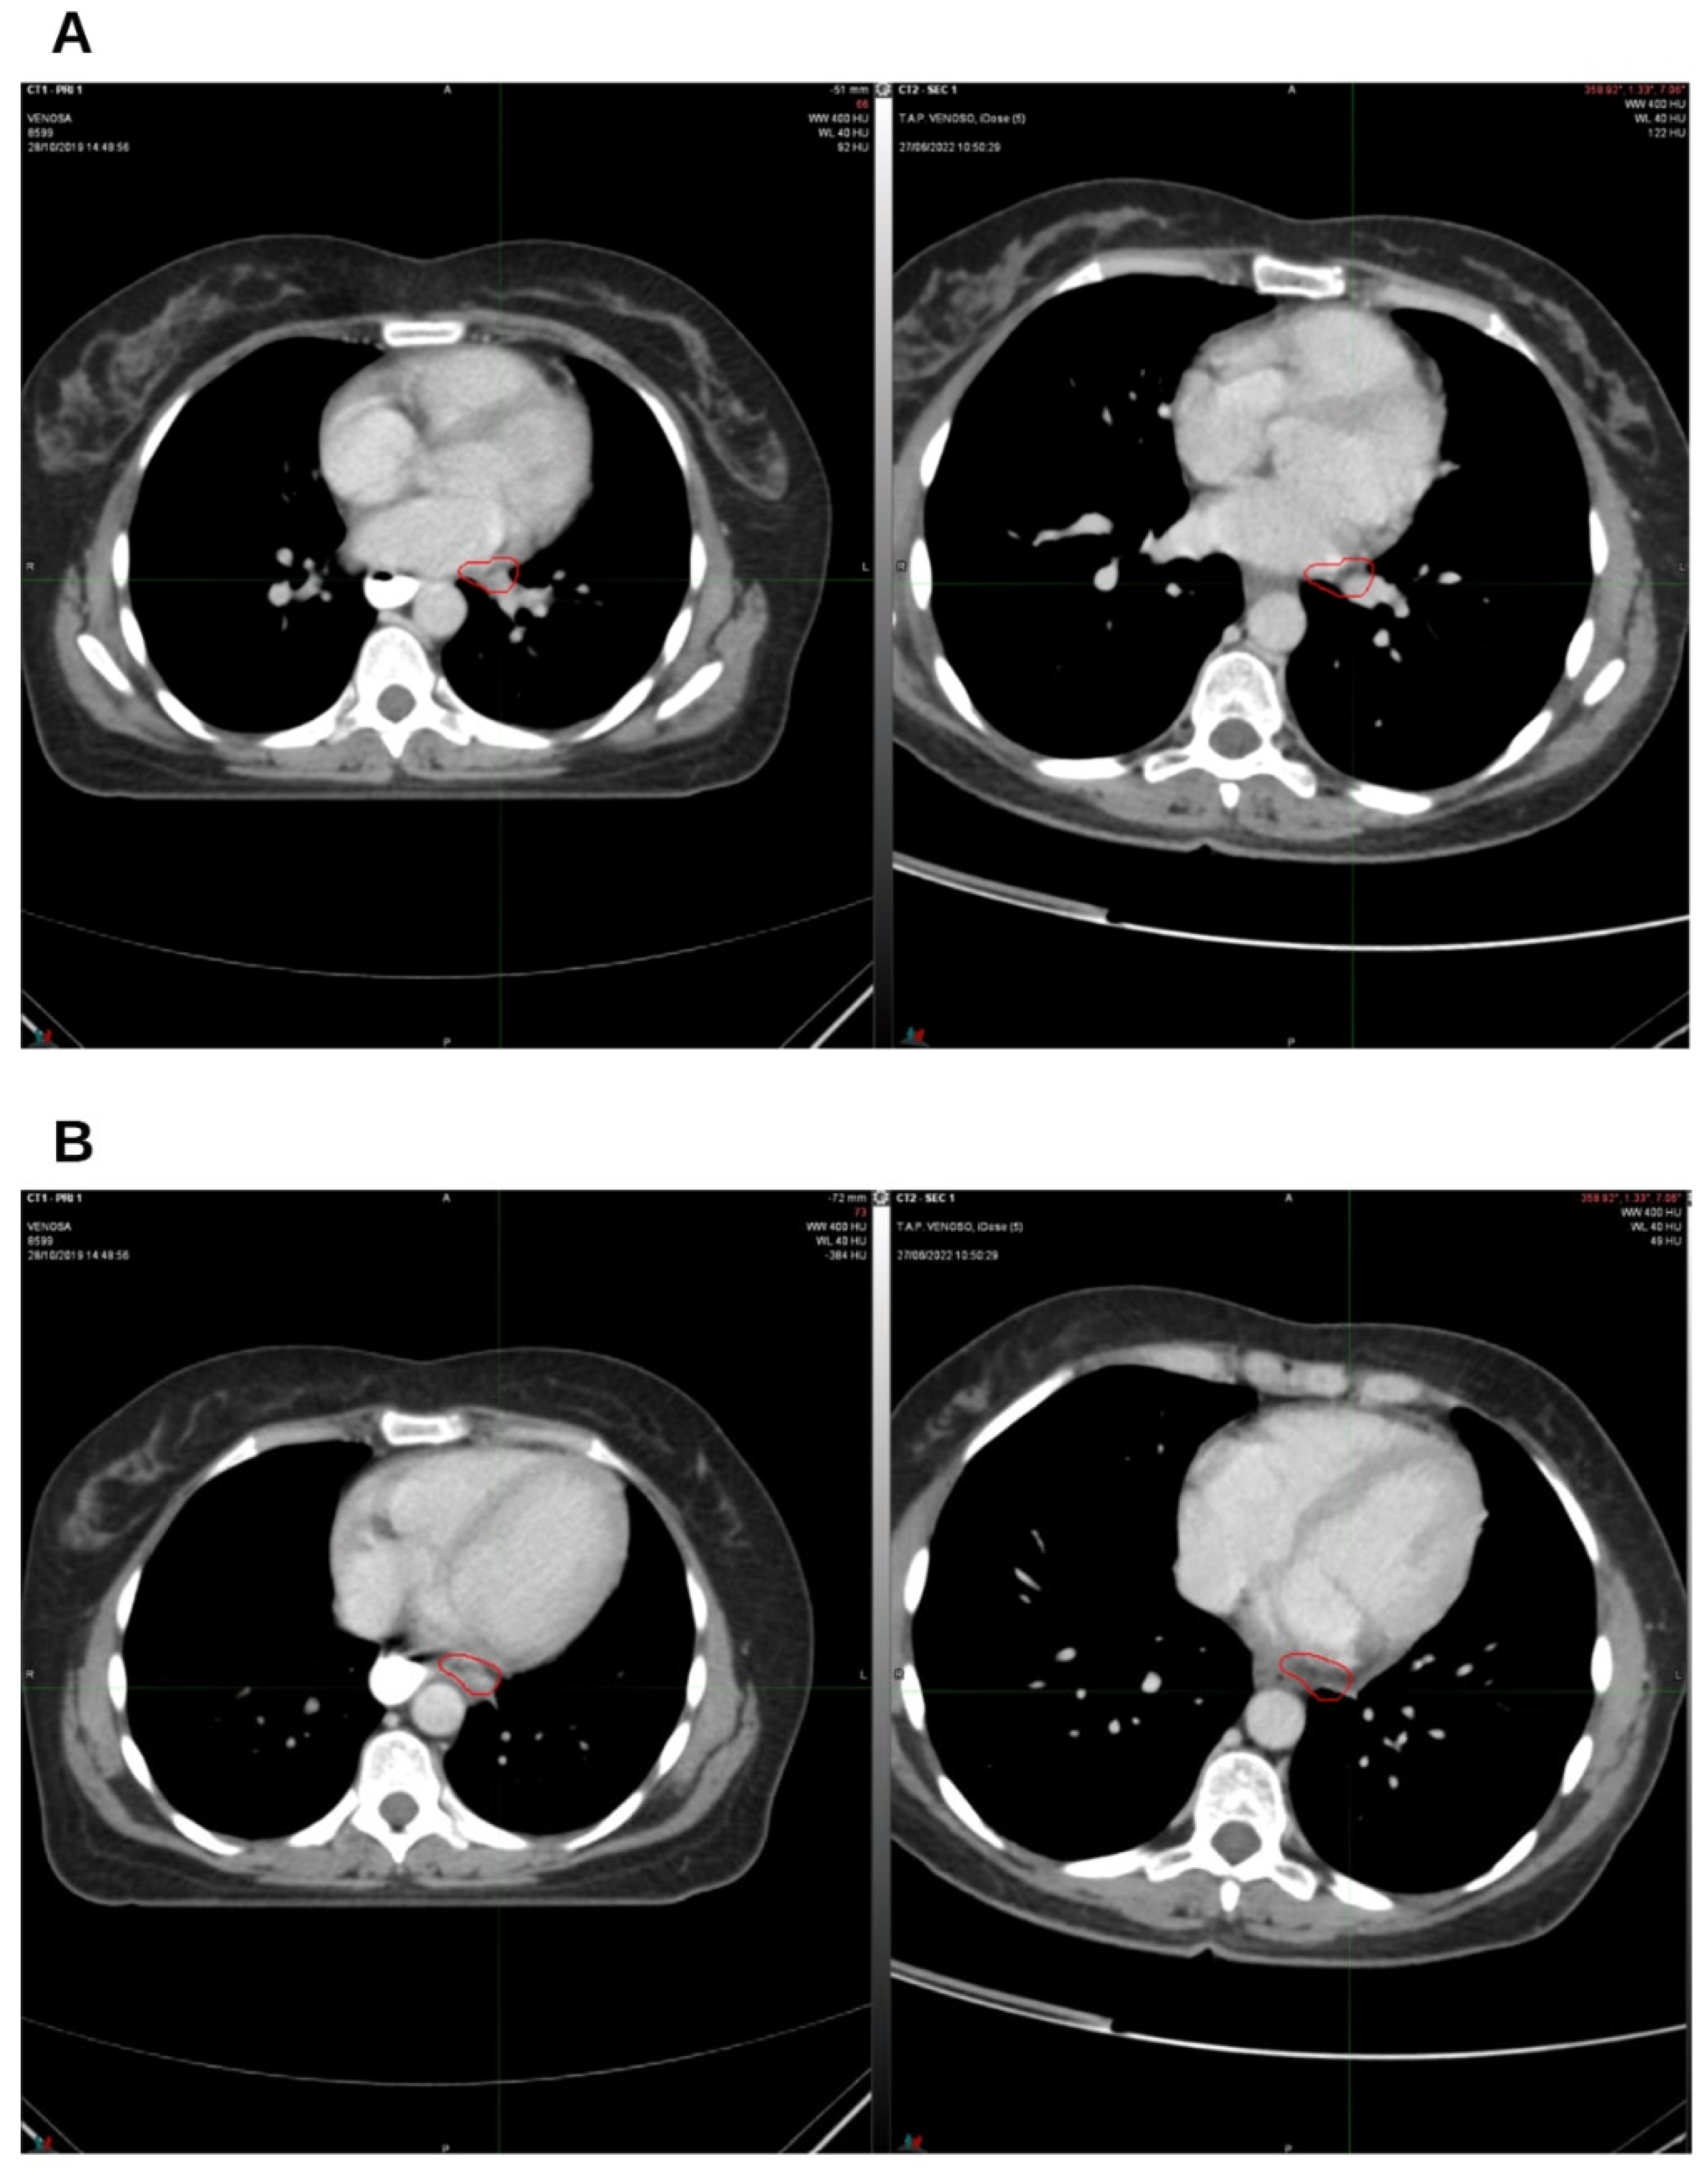

2. Case Presentation